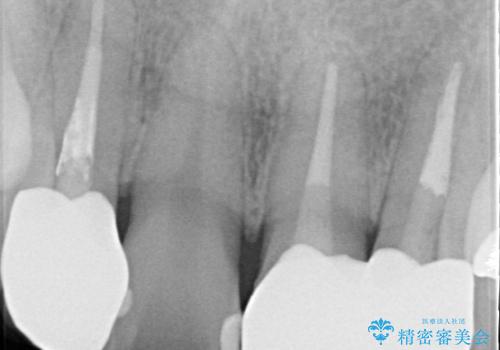

- 全体的なガタガタと前歯をきれいにしたいとのことで来院されました。

下の歯は重度のガタガタがあり、上の前歯は何本かが神経の治療がしてある状態でした。

インビザラインにて歯並びを整え、上顎の前歯にセラミックを装着する計画としました。